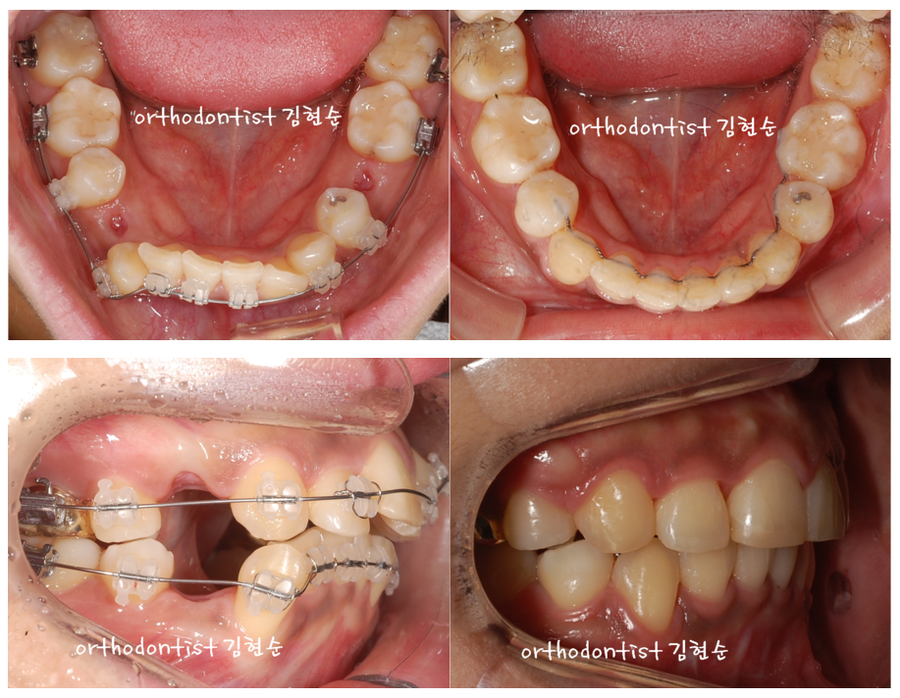

위 사진의 경우 여러 치열 상태가 문제가 되는 경우입니다.

먼저 송곳니가 바깥쪽으로 돌출되어 있고,

앞니 또한 돌출되어있습니다.

한쪽 송곳니가 배열에서 벗어나있기 때문에

그쪽으로 치아들이 몰려서

치아 중심선도 어긋나있습니다.

3M의 클라리티 세라믹 브라켓을 부착,

20 개월 교정 진행했습니다.

교정 전과 후의 비교사진입니다.

치아 중심선이 교정 전보다 오히려 반대쪽으로

이동한 것을 확인할 수 있습니다.